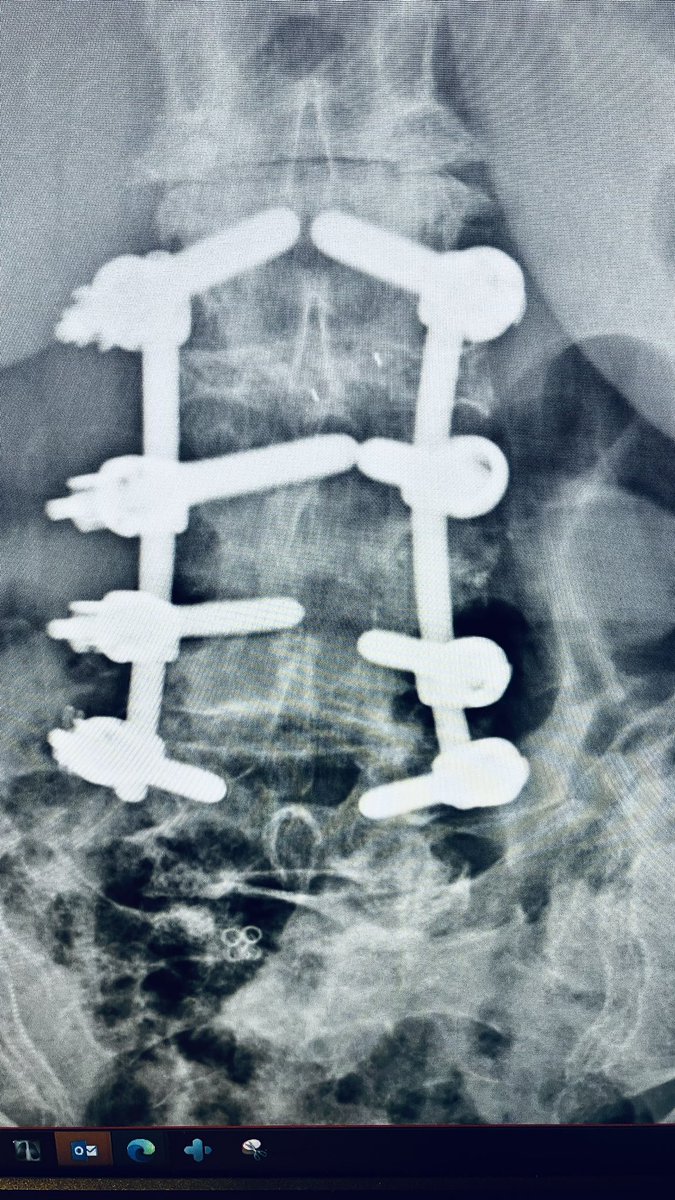

@atmghn There is a Facebook group dedicated to the identification of spinal implants. facebook.com/groups/3604528…